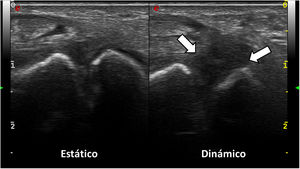

Imágenes de ecografía de muñeca con sonda lineal de alta frecuencia; abordaje dorsal. En la exploración estática (imagen izquierda), el espacio escafosemilunar impresiona de conservado, aunque se intuye una cierta hipoecogenicidad del ligamento escafosemilunar. Sin embargo, en la exploración dinámica (imagen derecha) se objetiva una marcada hipoecogenicidad con diástasis significativa escafosemilunar, sin identificar el ligamento con definición, en el contexto de su rotura.